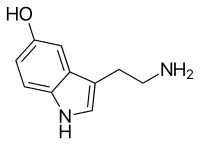

- Psilocybin mushroom (Psilocybe cubensis)